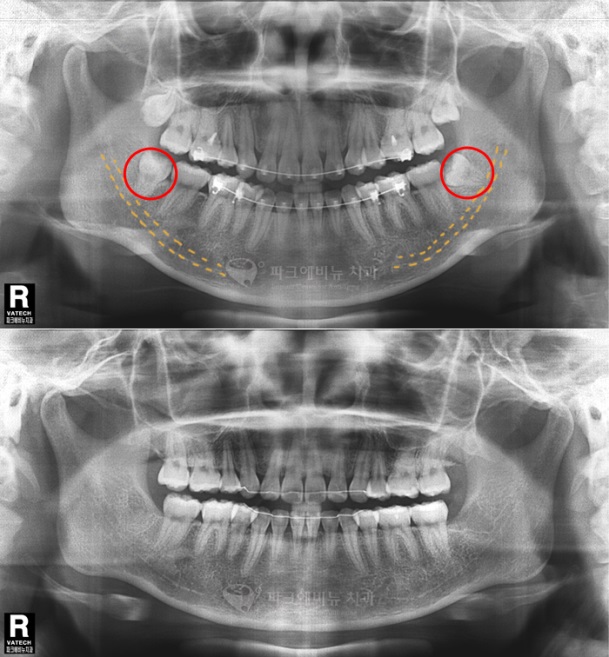

A. 사랑니는 좁고, 충분치 않은 공간에서 나기 때문에 대부분 제대로 나지 못하는 경우가 많아 통증을 동반합니다 어금니쪽으로 기울어져서 나거나 수평으로 자라게 되면 주변 치아나 신경을 건드리게 되어 통증을 느끼게 됩니다. 그 외 치아가 고르지 못하게 되면 음식물이 사랑니 뒤쪽에 끼게되어 칫솔질로 제거 되지 못해 치주질환등을 유발시키기 때문에 발치하는게 좋습니다.

A. 사랑니가 나지 않는 사람도 있습니다. 그러나 이미 나온 사랑니가 매복되어 본인도 모르게 자리잡고 있는 경우 나중에 문제가 되기 때문에 치과에서 검진해보시고 매복되어 있다면 발치하는게 좋습니다.